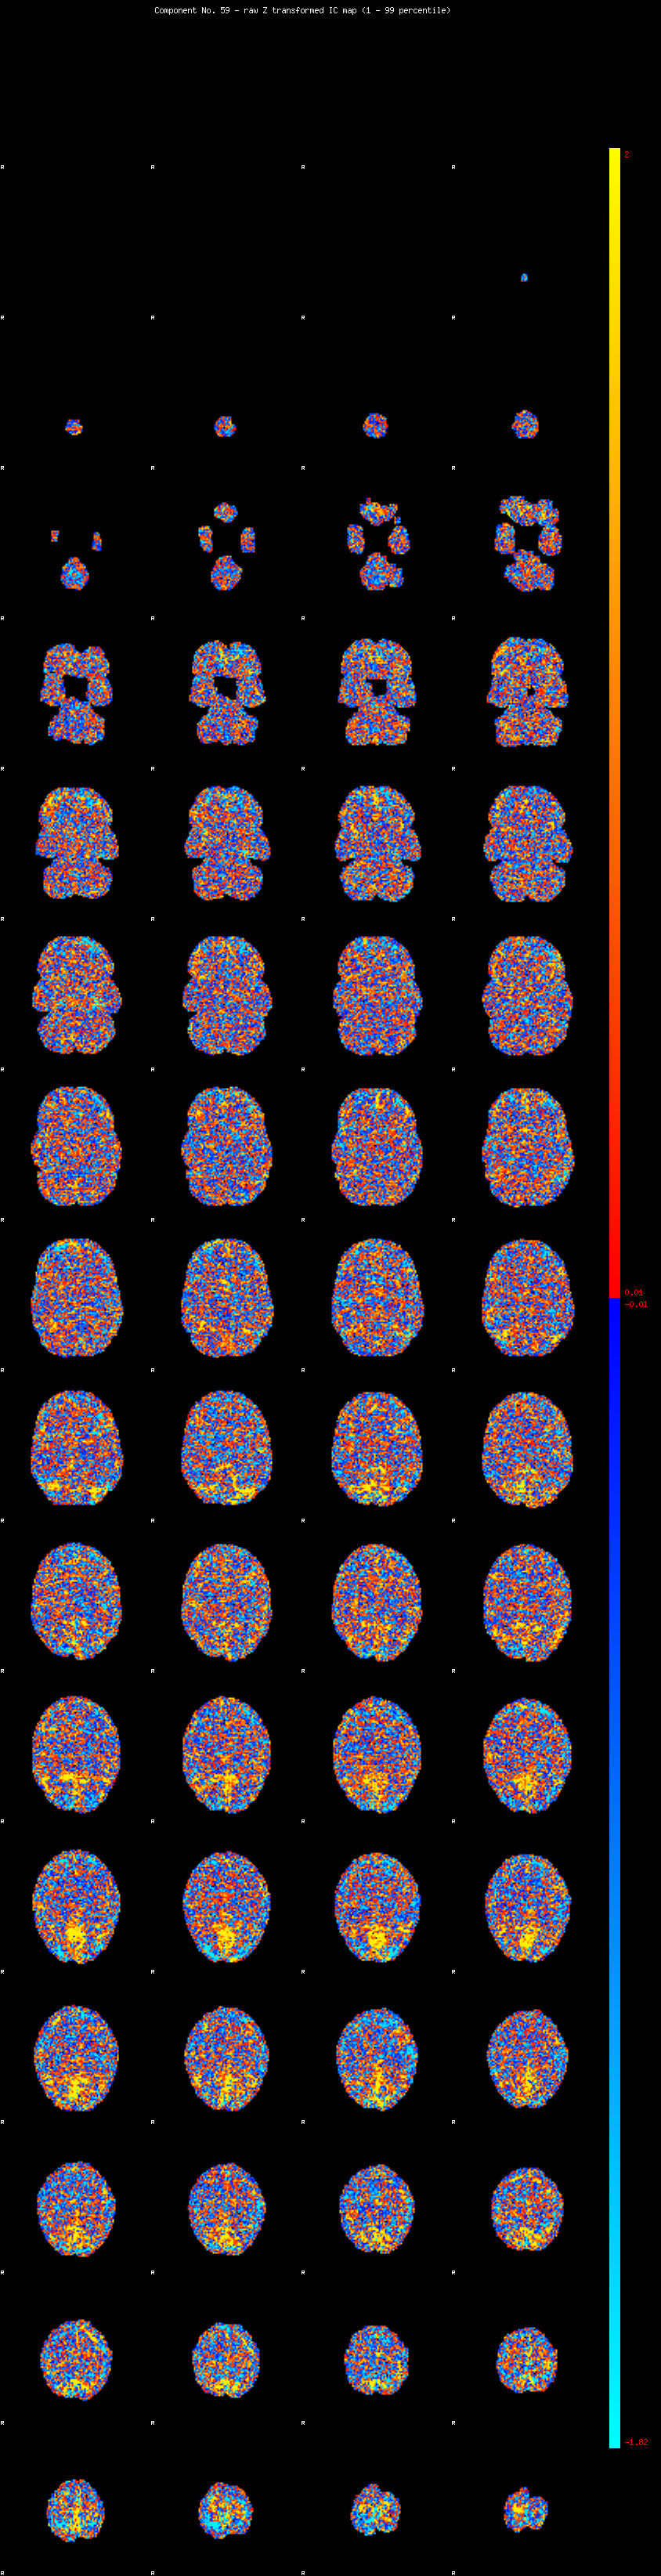

IC_59 Mixture Model fit

Means : 0.000000 2.808469 -2.919104

Vars : 1.000000 3.216771 0.901683

Prop. : 0.961846 0.028769 0.009385